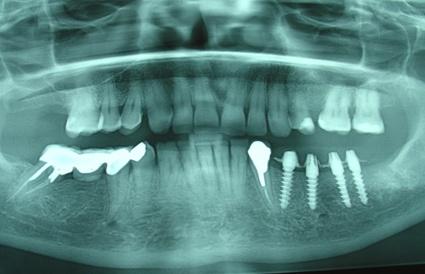

Para empezar, hay criterios clínicos y radiográficos condicionantes: poca encía adherida, boca seca, piezas dentales remanentes con piorrea, mala higiene oral por parte del paciente, etc. Radiográficamente: poco hueso tanto en longitud como grosor, sin maxilares muy neumatitzados, cantos a corte de cuchillo, osteoporosis, lesiones óseas, etc. A esto hay que sumarle el estado de salud general del paciente, enfermedades crónicas que dificultan o impidan la osteointegración del implante dental: diabetes descontroladas, hipotiroidismo, alcoholismo, drogadicción, psicosis, artritis reumatoide, pacientes sometidos a radiación de maxilares, pacientes que consumen usualmente bifosfonatos, entre otros.

Seamos sensatos, un paciente con dientes y muelas remanentes, sin movilidad puede llevar una prótesis fija, estética y confortable, sin ningún riesgo quirúrgico, hay un coste asumible en casi todas las economías familiares. Un desdentado total, si no puede o quiere llevar dentaduras postizas, y tiene hueso suficiente y ninguno de las contraindicaciones mencionadas anteriormente, puede llevar dientes fijos, siguiendo las recomendaciones y controles indicados por su dentista.